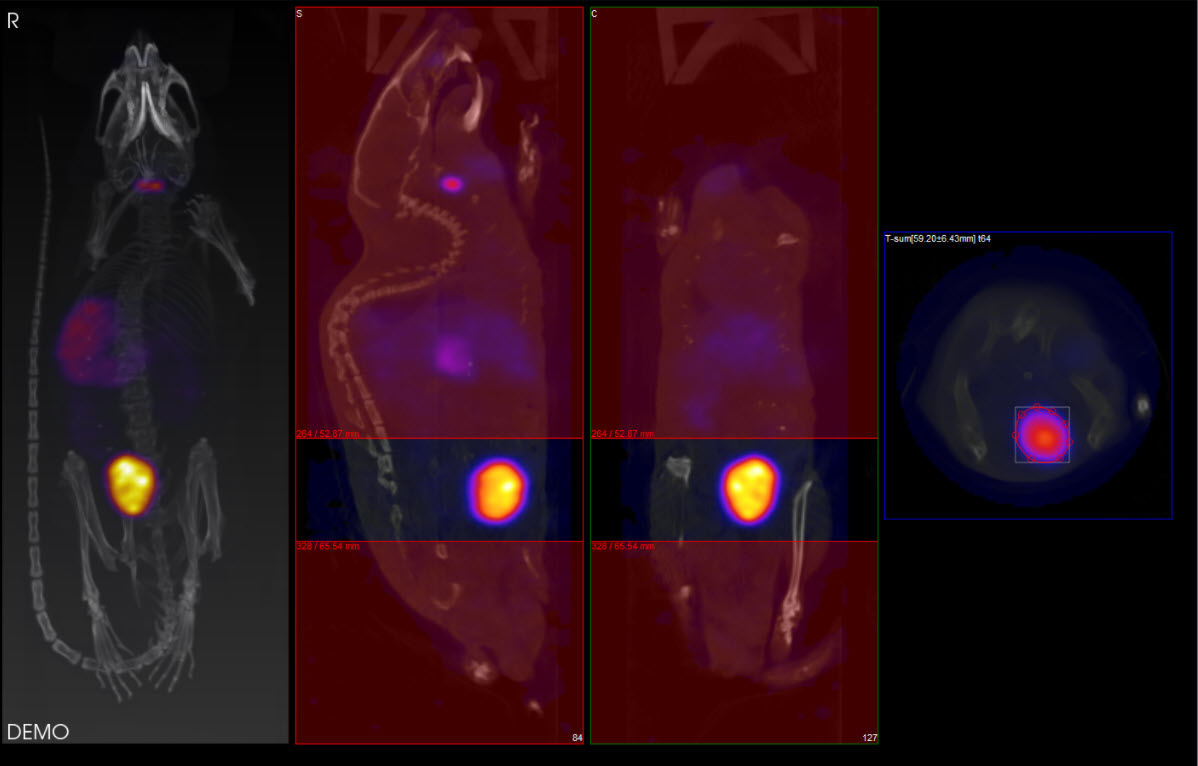

The ROI may be drawn in either the transverse (default), coronal, or sagittal plane. To toggle between these options, use the View menu in the Operator tab of the main menu.

In this example, using the default settings, the axial sliders determine the extent of the ROI in the axial direction. The region or pre-defined shape described below determines the bounds of the ROI in the transverse plane.

By using the View menu, it is also possible to draw ROI boundaries in the sagittal plane or coronal plane: